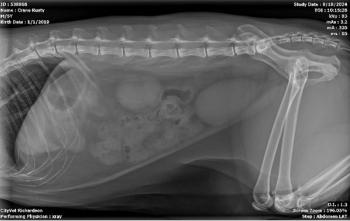

Lovey presented to the clinic lethargic, with inappetence but consuming plenty of water, and a bulge on her abdomen when lying down